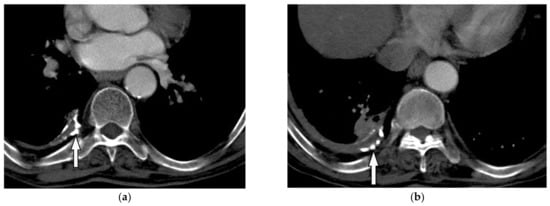

Imaging findings vary among different stages of the disease. The initial lytic active phase display osteolysis with no marginal sclerosis. While late blastic phase reveals cortical thickening and trabecular coarsening with bony enlargement. CT scan is useful in better delineation of the classic Paget’s disease triad: osseous expansion, cortical thickening, and trabecular coarsening (Figure 11) [35,37]. Fat-like signal intensity is the most common pattern of the Paget disease seen on MRI, indicating long-lasting disease. Other stage-specific MRI findings are explained in Table 2 [35,37]. The relationship between 18-F FDG uptake and Paget’s disease activity is still controversial, but a mild and diffuse pattern of FDG uptake is beneficial to differentiate it from bone metastasis [38].

Figure 11.

A 53-year-old woman with localized chest wall tenderness. The axial non-contrast CT in the bone window (a) and sagittal (b) images show enlarged vertebral body associated with trabecular coarsening, osseous expansion, and thickened cortex of right eighth rib (arrow).